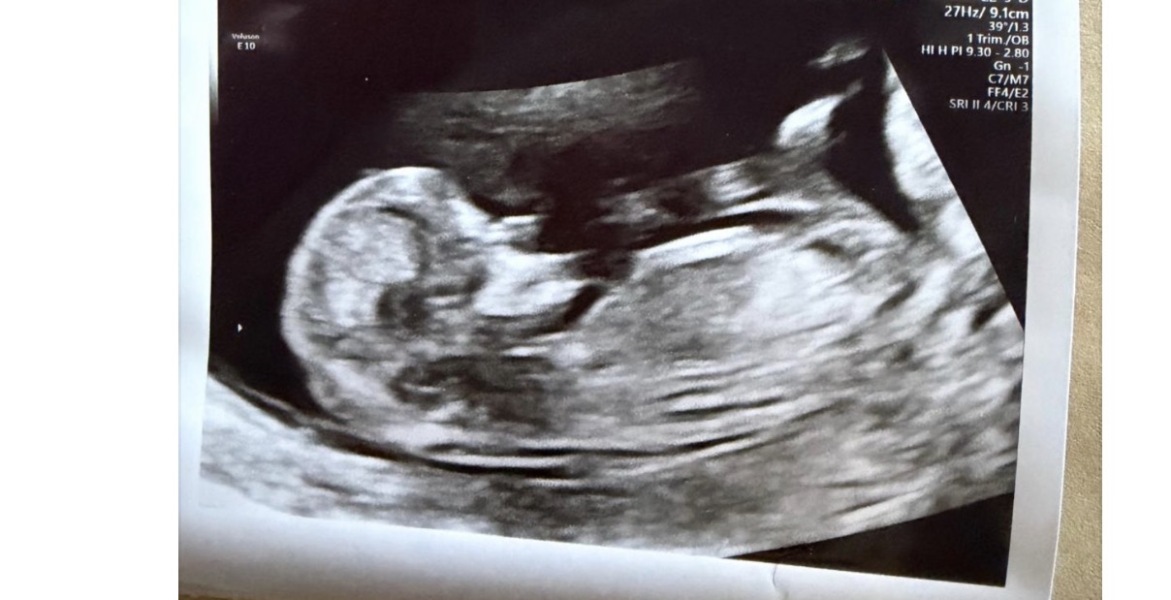

SZL · 14/08/2025 16:20

Had my scan 12 weeks and 5 days..told nub looks stacked but not clear. Would love your thoughts boy or girl

Nub theory guesses